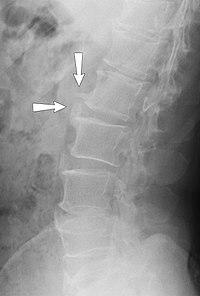

X-ray of spondylosis of the lumbar spine.

Workplace exposures to whole-body vibrations for long durations can lead to musculoskeletal problems of many kinds.[10] Problems of the neck and lower back in particular can be common for operators of heavy equipment including construction, forestry, agriculture, and trucking. Other occupations where whole-body vibrations may be present include aircraft operators, sea vessel workers, drivers of public transportation like trains and buses.

Farmers with long-term exposure to whole body vibration and mechanical shocks have a higher prevalence of back pain (compared to those not exposed to vibration), and the prevalence increases with vibration dose.[11] Long-term exposure affecting the whole body leads to spinal degeneration (spondylosis) and increased risk of low back pain.[12][13]